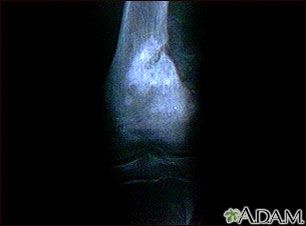

This x-ray shows a malignant bone tumor (osteogenic sarcoma) of the knee. This type of tumor is usually seen in adolescents (around 15 years old). This tumor extends from the bone into the surrounding tissue.